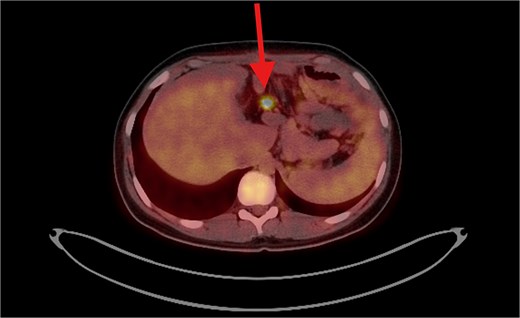

PET/CT scan showing a clear surgical bed. Almost complete metabolic resolution of the previous hypermetabolic abdominal deposits. Development of focal hypermetabolic activity just anterior and abutting the lower spleen pole, at the projection of splenic flexure of the descending colon, this lesion is nonspecific.